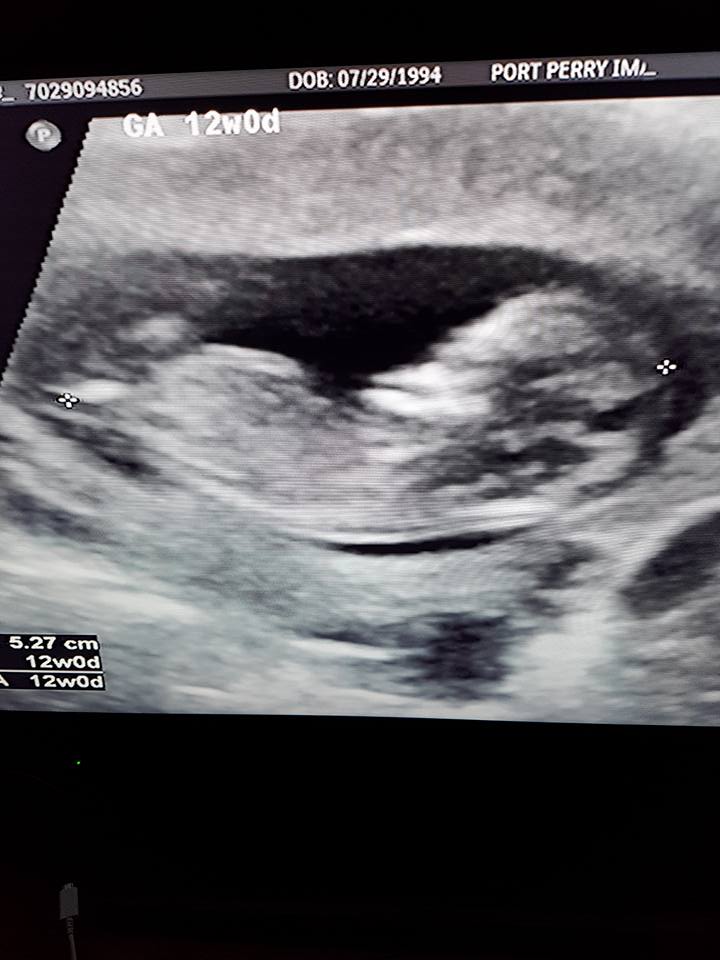

Hi! Just wondering if there is a nub in these photos, and if so, if you would guess it's a boy or girl? 12+0 weeks. Thank you!Attachment 38349Attachment 38350Attachment 38351Attachment 38352Attachment 38353